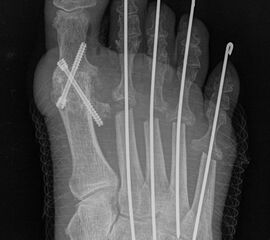

Deutlich bessere Ergebnisse wurden erreicht durch eine Kombination der OP nach Tillmann mit einer Arthrodese des Großzehengrundgelenks oder auch einer Lapidus-Arthrodese 611. Dies wurde bereits 1956 durch Vainio empfohlen, hat sich aber erst in diesem Jahrtausend flächendeckend durchgesetzt 121314.

Zum Lesen der Bildbeschreibung und zur Vollansicht bitte das Bild anklicken.